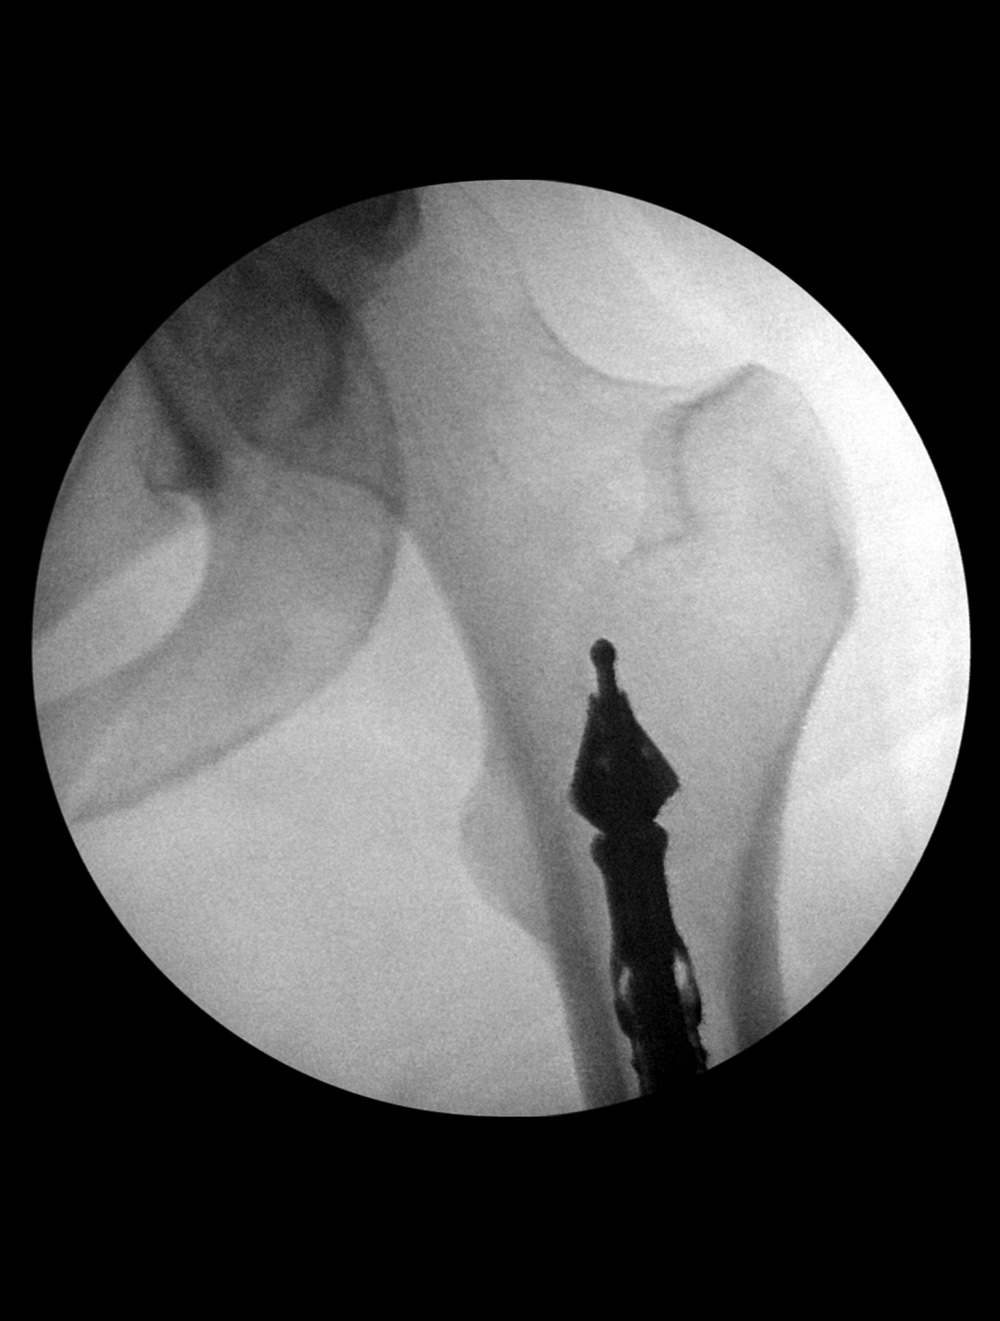

Bone graft harvesting

Bone graft harvesting Bone graft harvesting Bone graft harvesting postoperative image Bone graft harvesting postoperative image

41 year-old woman with left distal tibial pilon fracture with considerable bone loss. Bone graft harvesting to replace the lost bone was done from the left femur using a DePuy Synthes RIA intramedullary bone graft harvest system. The left two images show the reamer in the left femur. The right two images show postoperative gas (arrow) from the bone harvest site. Courtesy Kellon Hansen, MD.